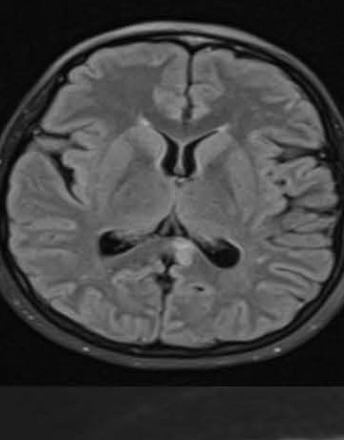

Susac syndrome in association with anti-GAD-65 antibodies

Susac syndrome is a rare autoimmune endotheliopathy characterized by encephalopathy, branch retinal artery occlusion (BRAO), and sensorineural hearing loss (SNHL). Due to its diverse presentation, it is often misdiagnosed. We report a case of a 22-year-old female with progressive neurological symptoms, hearing loss, and cognitive dysfunction. Brain MRI revealed characteristic corpus callosum “snowball” lesions, and further investigations confirmed BRAO and SNHL.